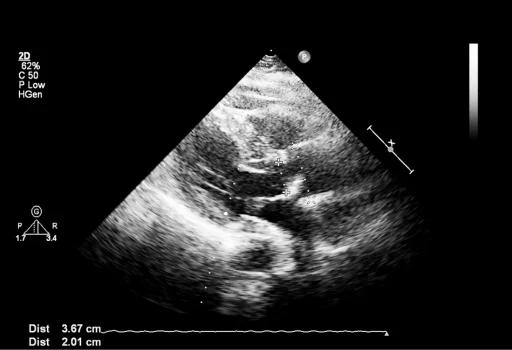

Fetal echocardiography

Done between16-32 weeks . It is usually preferred to do it around 22-24 weeks when the heart of the fetus is big enough and abnormalities can be detected. It is recommended in patients who have parents , previous child or family member with congenital heart abnormalities , mothers with medical complications like diabetes or SLE, or suspicion in previous scan. It is a detailed examination of the structure and function of the heart of the fetus to rule out abnormalities like holes in the heart , abnormal valves or chambers or vessels connecting in the heart.